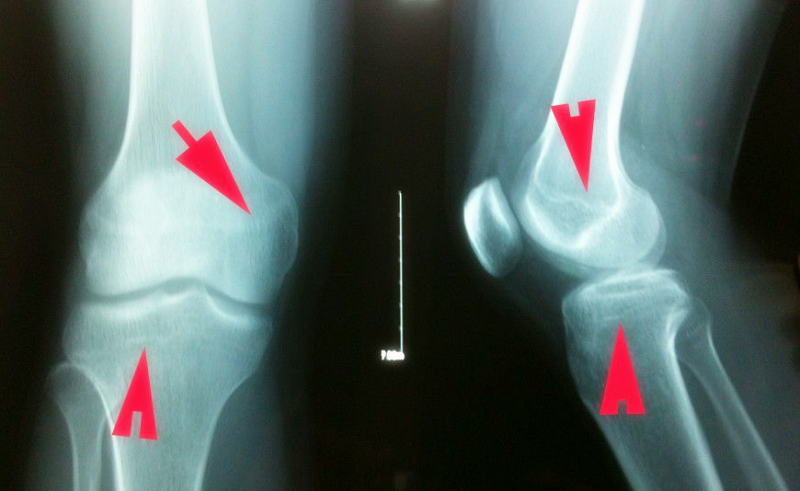

要具体了解孩子的骨骺线是否闭合通常只需要去医院拍一个左手腕关节(16周岁以下)或左侧膝关节(16周岁以上)的正位片。骨骺线没有闭合,长高空间很大,一年每年可长10cm;骨骺线半闭合,生长空间也还有,每年大概可以长6-7cm;骨骺线接近闭合,生长速度开始减慢,每年大概长1-3cm;骨骺线完全闭合,则没有长高空间,身高停止增长。因此,孩子要增高,一定要赶在骨骺线闭合前。